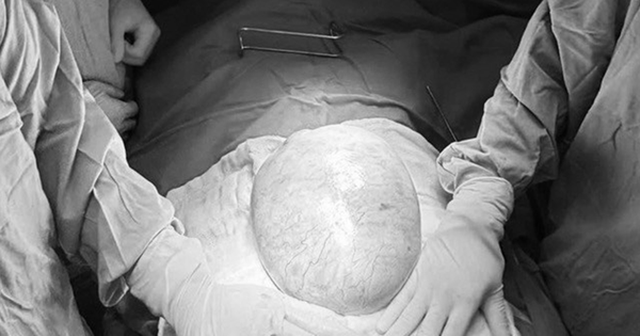

Khối u buồng trứng khổng lồ ở bệnh nhi. Ảnh BVCC.

Khi nhập viện, bác sĩ ghi nhận bụng bệnh nhi mềm, xuất hiện khối vùng hạ vị phát triển vượt qua rốn, ấn không đau. Các xét nghiệm dấu ấn khối u như AFP và beta-hCG đều trong giới hạn bình thường. Tuy nhiên, siêu âm và chụp CT cho thấy, một khối u ổ bụng rất lớn, kích thước khoảng 18-25cm, cấu trúc hỗn hợp gồm dịch và mô đặc. Bên trong khối u có vách, vùng mô đặc, vôi hóa và mô mỡ, gợi ý khối u xuất phát từ buồng trứng phải. Khối u còn chèn ép niệu quản phải, gây giãn niệu quản và thận phải ứ nước.

Theo BS.CKI Nguyễn Hiền (Khoa Ngoại Tổng hợp, Bệnh viện Nhi đồng 2), khi tiến hành phẫu thuật, các bác sĩ ghi nhận khối u có kích thước khoảng 20x25x10cm, nặng gần 4kg, chiếm gần toàn bộ buồng trứng phải. Do khối u lớn, có thành phần mô đặc và nguy cơ ác tính, ê-kíp quyết định cắt trọn buồng trứng phải cùng vòi trứng phải nhằm loại bỏ hoàn toàn tổn thương. Ca phẫu thuật diễn ra thuận lợi, bệnh nhi hồi phục tốt sau mổ.